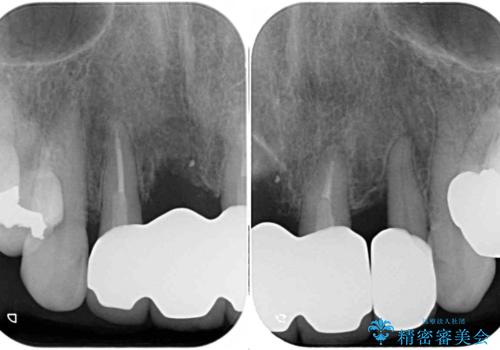

また、前歯に抜歯が必要な歯があったため、抜歯をし、傷の治りを待ってオールセラミックブリッジにて補綴治療を行うこととしました。

一番気になっていた隙間が埋まり、不快感から解放されました。